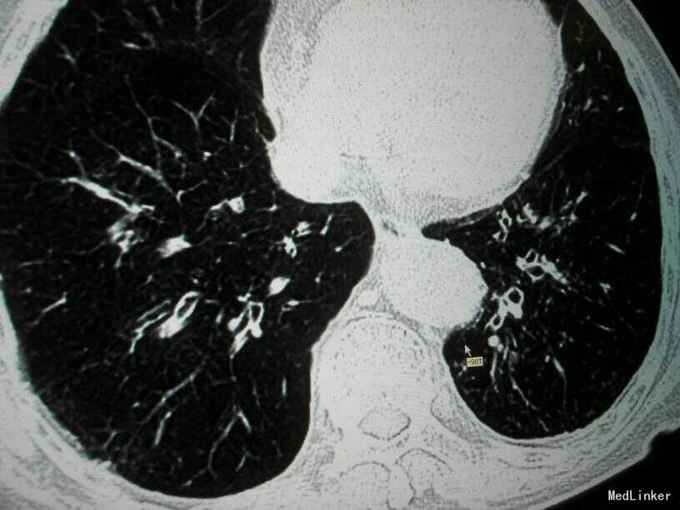

查体:唇指发绀,桶状胸,肋间隙增宽,双肺叩诊呈过清音,双肺呼吸音粗,可闻及散在干湿性啰音,未闻及明显湿性罗音,呼气延长,心腹阴性,双下肢轻度水肿。 辅助检查:入院后血气分析 PH 7.41 PCO2 43mmHg,PO2 73mmHg,BE 2.7mmol/L SO2:96%;心电图:室性早搏;胸片:符合慢支合并双肺炎症;肺CT示1.两肺多发支气管扩张并感染2.两肺间质纤维化,两侧胸膜增厚;心脏彩超:肺动脉压增高,肺动脉略宽;痰培养:肺炎克雷伯杆菌亚种;

诊断:慢阻肺急性发作;支气管扩张并感染;肺间质纤维化;慢性肺心病 治疗经过:抗炎:哌拉西林他唑巴坦;化痰:羧甲司坦口服液+盐酸氨溴索针;解痉平喘:多索茶碱,复方异丙托溴铵雾化溶液+布地奈德雾化混悬剂,雾化吸入;扩冠、减轻心脏负荷:硝酸甘油针;利尿:拖拉塞米针;3日后停硝酸甘油,改单硝酸异山梨酯缓释片口服,后患者出现胸闷、胸痛、气短症状加重,请心内科会诊后,给予呋塞米20㎎,隔日1次口服;螺内酯片20㎎,1日1次;替米沙坦片40㎎ 1日1次;美托洛尔6.25㎎;氯化钾缓释片 0.5g,1日2次;并给予抗血小板聚集、调脂、稳定斑块等治疗;治疗10天后,患者受凉后出现畏寒、发热,侧体温38.1℃,停哌拉西林他唑巴坦,改为盐酸莫西沙星针0.4g,1日1次,其余治疗同前;治疗3天后患者体温恢复正常,偶有咳嗽,咳少量白色黏痰,症状好转,出院。